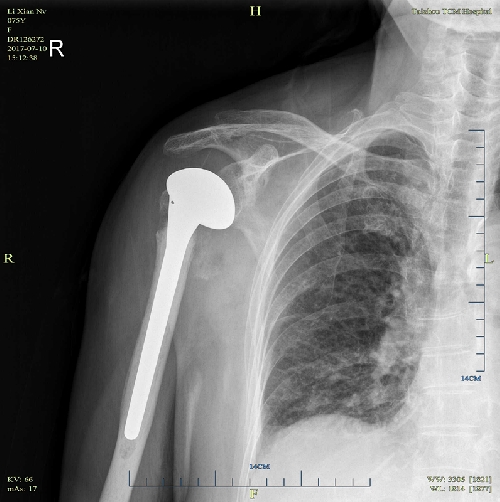

術(shù)后X片正位 術(shù)后穿胸位

患者術(shù)后肩部疼痛明顯緩解,并在骨三科醫(yī)生的悉心指導(dǎo)下,術(shù)后一周肩關(guān)節(jié)已能被動(dòng)外展90°。